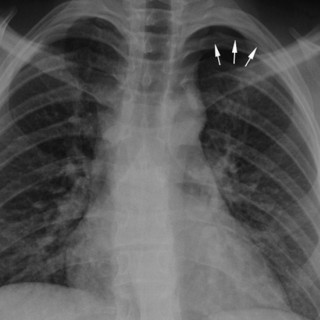

Pulmonal hypertensjon er en kompleks og multidisiplinær sykdom, der klassifisering og retningslinjer for diagnostikk og behandling ble revidert i 2009 (1, 2). Middeltrykket i arteria pulmonalis er per definisjon ≥ 25 mm Hg i hvile bedømt med høyresidig hjertekateterisering. Ved prekapillær form for pulmonal hypertensjon (gruppe 1, 3, 4, og 5) er innkilt lungearterietrykk ≤ 15 mm Hg og reflekterer normale trykk i venstre atrium. Dette er i motsetning til postkapillær pulmonal hypertensjon med > 15 mm Hg (gruppe 2), som uttrykk for økt fylningstrykk på venstre side av hjertet. Inndelingen i fem...